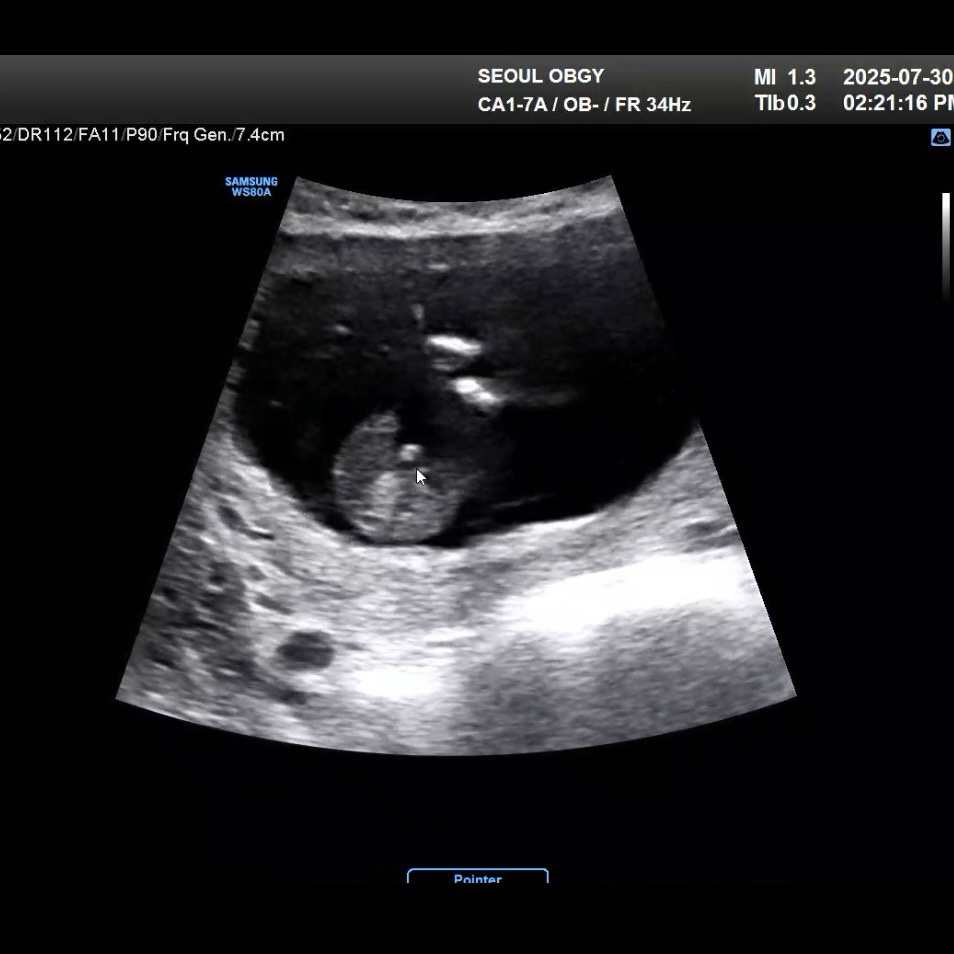

의사선생님도 모르겠대요.. 14주차 초음파 성별

매끈하게 보이는 사진도 있는데 옆에서 보면 저렇게 튀어나왔어요.. 선생님도 너무 헷갈리신다고 하네요! ㅠㅠ 뭘까요?..

아들일것같은데용 탯줄이아니라면요!!